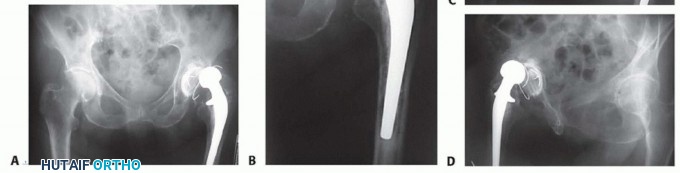

Antibiotic Spacer Fabrication and Placement

An antibiotic-loaded PMMA spacer is inserted to maintain soft tissue tension, preserve dead space, and deliver high local concentrations of targeted antimicrobials. Spacers may be articulating or static. Articulating spacers improve patient mobility and facilitate the second-stage exposure, whereas static spacers are reserved for cases with massive bone loss or abductor deficiency where stability is compromised.

High-dose antibiotic cement is prepared, typically mixing 3 to 4 grams of Vancomycin and 3.6 grams of Tobramycin per 40-gram batch of PMMA. The antibiotics must be in powder form and heat-stable. The spacer is molded and inserted into the femur and acetabulum.

Stage Two Reimplantation

The second stage involves the removal of the spacer, a final debridement, and definitive arthroplasty reconstruction.

The joint is re-exposed, and the antibiotic spacer is extracted. Intraoperative frozen sections may be utilized to assess for persistent acute inflammation; greater than 5 to 10 PMNs per high-power field suggests ongoing infection, which may necessitate an abortive procedure and a repeat spacer placement.

If the frozen section is negative, the reconstruction proceeds.